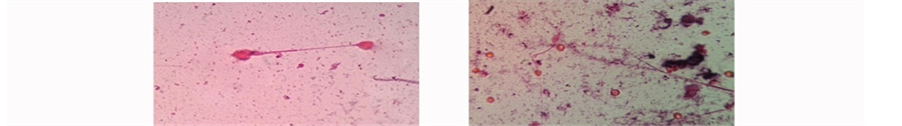

1.5%. And very long tail and circular head of sperms at 2.0% as it was administrated in Figure 2. In mice treated with Citrullus colocynthis seed extract, the sperms at 0.5% and 1.0 were normal. While at 1.5%, two heads attached to one tail and small, circular head attached to long tail at 2.0% as in Figure 3. The effect was dose dependant, that is the higher the dose the greater the effect. The fact that the extract contained some pro- oxidants like flavonoids, saponnins, anthraquinones, alkaloids and terpenoid suggests that the administration of the extract at higher doses of 100 - 1000 mg/kg body weight for two weeks may lead to oxidative damage due to free radical (FR) and reactive oxygen species (ROS) generation. The defect in sperm morphology detected in mice administered with the extract at higher doses demonstrated that the extract may have direct effect on sexual glands and sperm cells beside it pro-oxidant effect.

Figure 3. Observation of sperm shape and size of mice under the microscope treated with Citrullus colocynthis at different concentrations (40´): (a) Control; (b) 0.5%; (c) 1.0%; (d) 1.5%; (e) 2.0%.